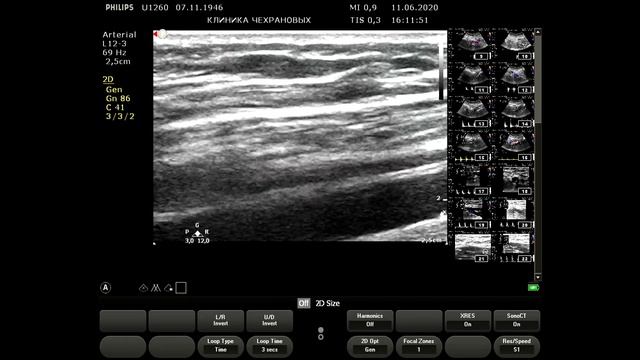

Болезнь отсутствия пульса. По научным данным данное заболевание встречается 26 случаев на 1 млн населения. В видео я ошибся говорю 3 случая на 100 тыс населения. Таким образом в Уссурийске где населения 200 тыс- это прям редкость просто я наблюдаю двоих таких пациентов и мне кажется чт они должны быть чаще. Коллеги вы встречали этот синдром в совей практике ? Итак пациентка прооперирована: протезирование левой общей сонной артерии по поводу окклюзии в 2022 году. В 2024 году возник рестеноз- в проксимальном сегменте возник гемодинамически значимый стеноз как подключичной артерии так и проксимального отдела шунта и мы наблюдаем коллатерализацию кровотока в левой подключичной артерии и разность АД а также снижение скорости и характера кровотока в протезе левой ОСА и в ВСА. Брахиоцефальный ствол также поражен но стеноз не более 40 незначимый. Правая общая сонная артерия идаельная ТИМ 045 мм. Вот такой случай. Наш whats app: 89143382293,